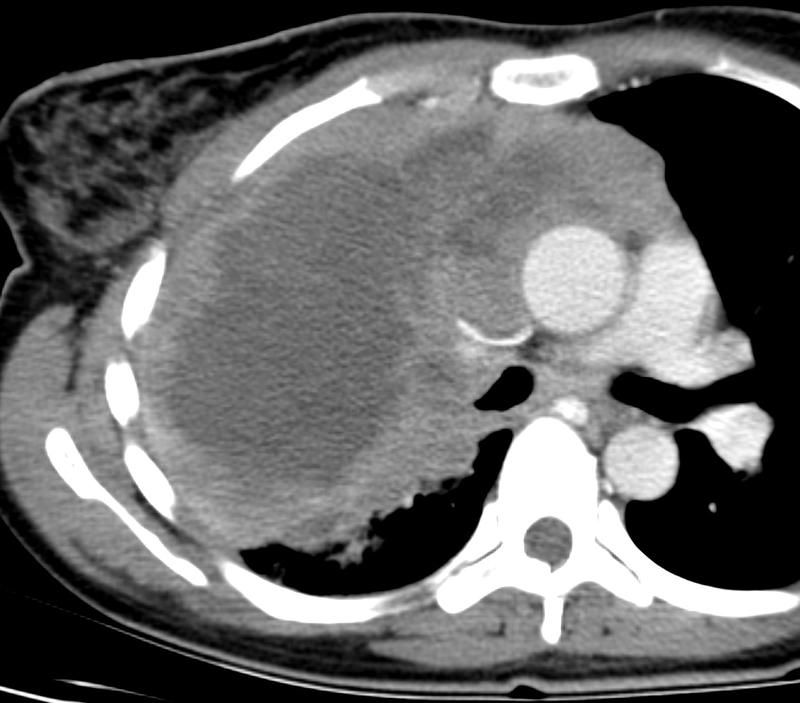

Mediastinum

Lymphoma

Lymphoma axial CT